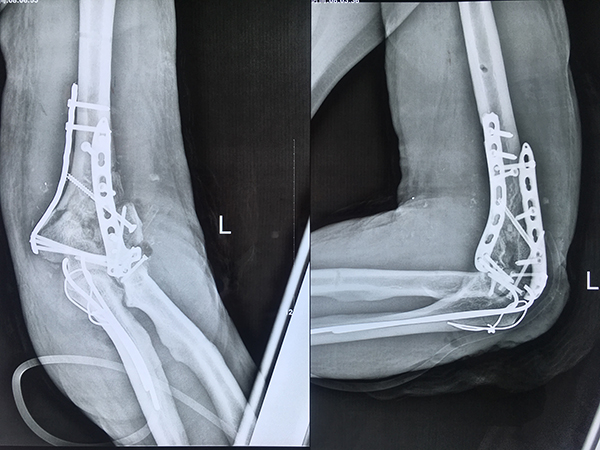

在經(jīng)過縝密的術(shù)前討論后,4月21日,由柳州市人民醫(yī)院派駐我院的醫(yī)聯(lián)體專家——骨科主任王棟棟主刀,醫(yī)院骨科一病區(qū)副主任陳鴻潔協(xié)助,共同為患者實施該手術(shù)。術(shù)中,王主任成功將患者的部分髂骨取出,結(jié)合患者殘留的骨質(zhì)及部分關(guān)節(jié)軟骨,重建肱骨遠端的滑車關(guān)節(jié)、球窩關(guān)節(jié)及骨性結(jié)構(gòu),恢復肱骨遠端的正常解剖角度。由于手術(shù)過程十分復雜,整臺手術(shù)耗時近5個小時才順利完成。

圖為 患者術(shù)后左肘部位圖示